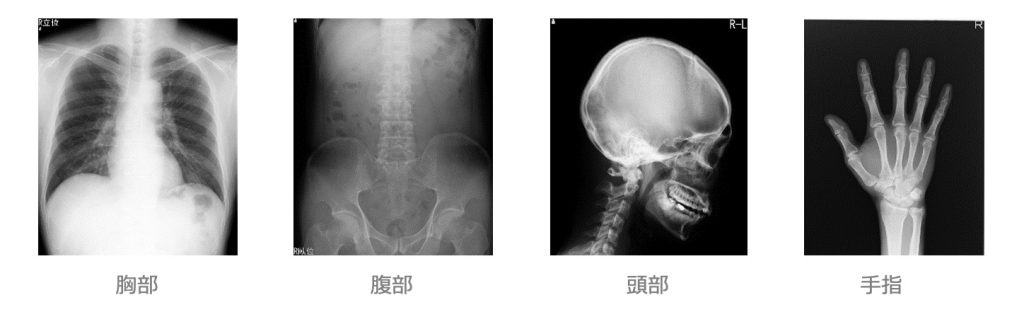

単純X線撮影検査

- X線を使用し胸部や腹部、骨の状態を撮影します。

- 撮影部位によっては検査衣への着替えが必要です。

- 撮影部位(特に胸部、腹部撮影)によっては、呼吸を止めて撮影することもあります。

- 検査室へのご案内は、受付番号でお呼びします。

検査内容によっては撮影順番が前後することがありますのでご了承ください。

●ご注意頂きたいこと

- 貴⾦属(ネックレス、ピアスなど)

- ⼊れ⻭、眼鏡

- ブラジャー(⾦属の⼊ったもの)

- ズボンのベルト、ファスナー

- 湿布、カイロ、エレキバン

- プラスチック類(下着のアジャスター、ボタンなど)